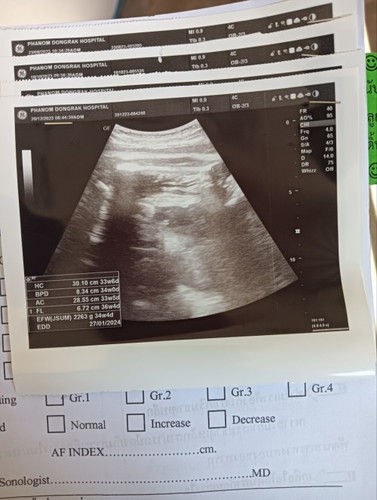

ตอนนี้36w4dน้ำหนัก 2263เองตะหมอบอกตามเกณตุ2500 เเต่เหลืออีกอีก1เดือนน้ำหนักจะขึ้นไหมคะ

ตอนนี้36w4dน้ำหนัก 2263เองตะหมอบอกตามเกณตุ2500 เเต่เหลืออีกอีก1เดือนน้ำหนักจะขึ้นไหมคะ พ่อเเม่เป็นคนตัวเล็กกินไม่เคยขสดเเต่น้ำหนักก้ไม่ค่อยขึ้นเลย คะ กังวลมาคะ หมอบอกเกิดมาจะตัวเล้กตัวเหลือง